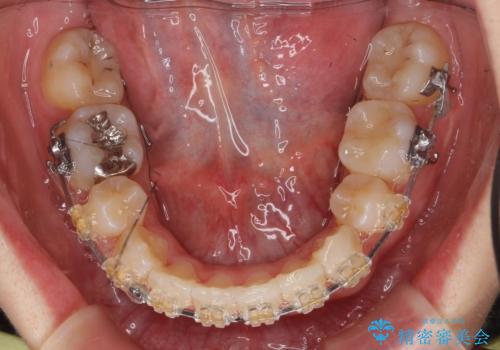

八重歯の治療 仕上がり重視で

- 矯正装置

- 審美装置

- 八重歯を主訴に来院。

仕上がり重視とのことで、小臼歯を抜歯し、スタンダードな治療方法で仕上げています。

上下の小臼歯を抜歯しています。

矯正用インプラントアンカーを使用してしっかり前歯を下げたため、口元が大きく改善しています。